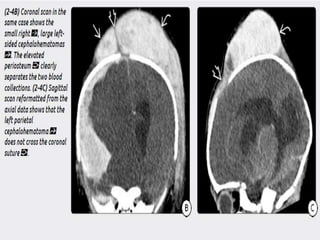

2) Hematoma- cephalohematoma and subgaleal

hematoma. The latter is more severe n can

cause hypovolemia and hypotension.